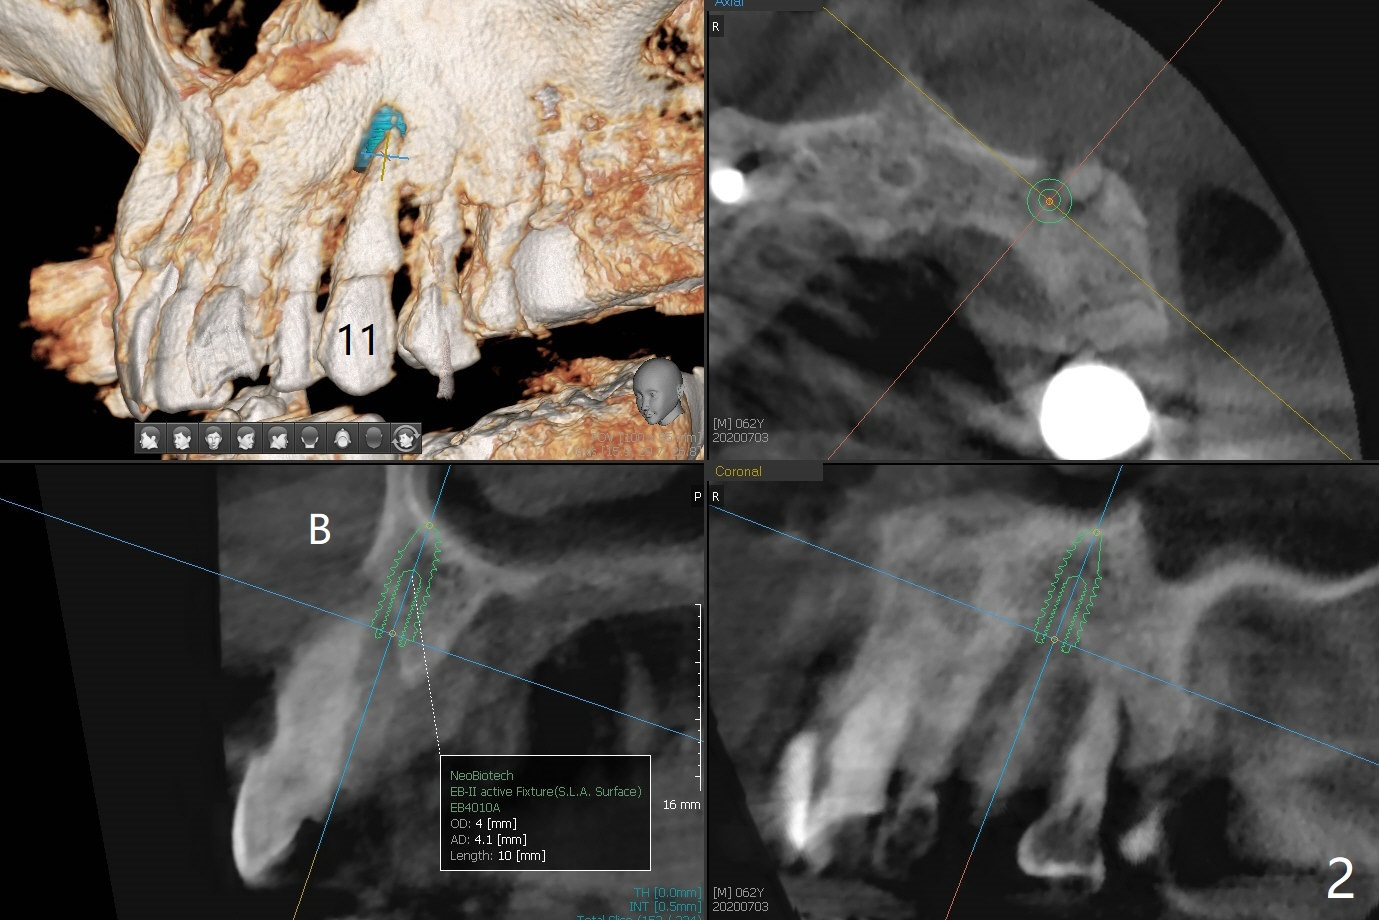

A 62-year-old man with generalized chronic periodontitis returns with chief complaint of loose tooth at #11 (Fig.1). Although a buccal fistula (Fig.1 <) is closer to #12 than to #11, percussion is more severe at #11 than 12. The buccal plate of #11 is missing, but it is possible to place a narrow immediate implant because of the wide alveolus (Fig.2). Since the gingiva is ~ 10 mm long, a mill abutment is to be used (Fig.3,5). In fact the fistula communicates with #11 extraction socket. After debridement, osteotomy is initiated (Fig.4) for a 3.8x10 mm implant ~ 35 Ncm, followed by seating a 4.5x2 mm mill abutment (Fig.5). Abundant sticky bone is placed in the remaining socket (for buccal plate reconstruction) and against the root surface of the neighboring teeth (Fig. 6 * (#10,12)). Finally 2 pieces of PRF membranes are utilized to facilitate repair of the buccal soft tissue defect (Fig.7 *). The root prominence of the canine seems to be maintained by the bone graft (Fig.8 C). Acrylic dressing holding the PRF membranes in place remains in situ with the healthy gingiva buccal (Fig.9) and palatal (Fig.10) 11 days postop. Note the acrylic locking into the undercuts of the neighboring teeth (*). 经过一段摸索发现离心每分钟1500转5分钟后,抽取上清液,接着再离心10分钟剩余上清液就形成血小板块,压制后便是血小板膜,后者似乎有助于软组织愈合,而上清液用来制备骨块,帮助硬组织生长。利用这个原则讨论以下病例治疗。The gingival margin gains ~ 5 mm 6 weeks postop when the acrylic dressing is removed (Fig.11,12 (<: previous one), as compared to Fig.7,8). 治疗结束时尖牙牙龈缘高于第一双尖牙(图七,八),六个星期后,尖牙牙龈缘却低于双尖牙(图十一,十二(箭头:原始牙龈缘))。术后2.5,4.5月基台周围牙龈似乎能与钛合金附着,防止细菌进入深部植体(图十三,十四)。临时牙冠脱落多次,可能与mill abutment太光滑有关,所以颊侧,舌侧磨成平面(图十四)。取模时好像不必取出基台清洗(仿佛没有炎症),原位用树脂延长基台。术后5个月CT显示颊侧骨板再生(图十六-十八)。取模时并没有用树脂加长基台;粘固时,牙冠颜色理想,但是照片中并不是如此(图十九,二十),颊侧骨板没有塌陷。术后11个月基台颊侧骨板没有萎缩(图二十一:B);3d图像:骨壁完全形成(图十六对比:部分形成)。密度也增高(图二十二:B),与术后五个月比较(图十七)。术后十一个月,粘固后五个月角化龈存在(图二十三),牙冠颈部有金属颜色透出,是因为二段式基台太粗了(最细4.5毫米),可以请实验室在牙冠内部涂opaque material而减轻。